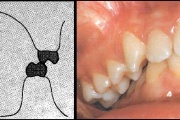

Ravijärgne seis. Jäävhammas on täielikult lõikunud.

) Röntgenülesvõte. Ülemise esimese jäävmolaari lõikumine on takistatud 2. piimamolaari tõttu

Esimese jäävmolaari ektoopiline lõikumine